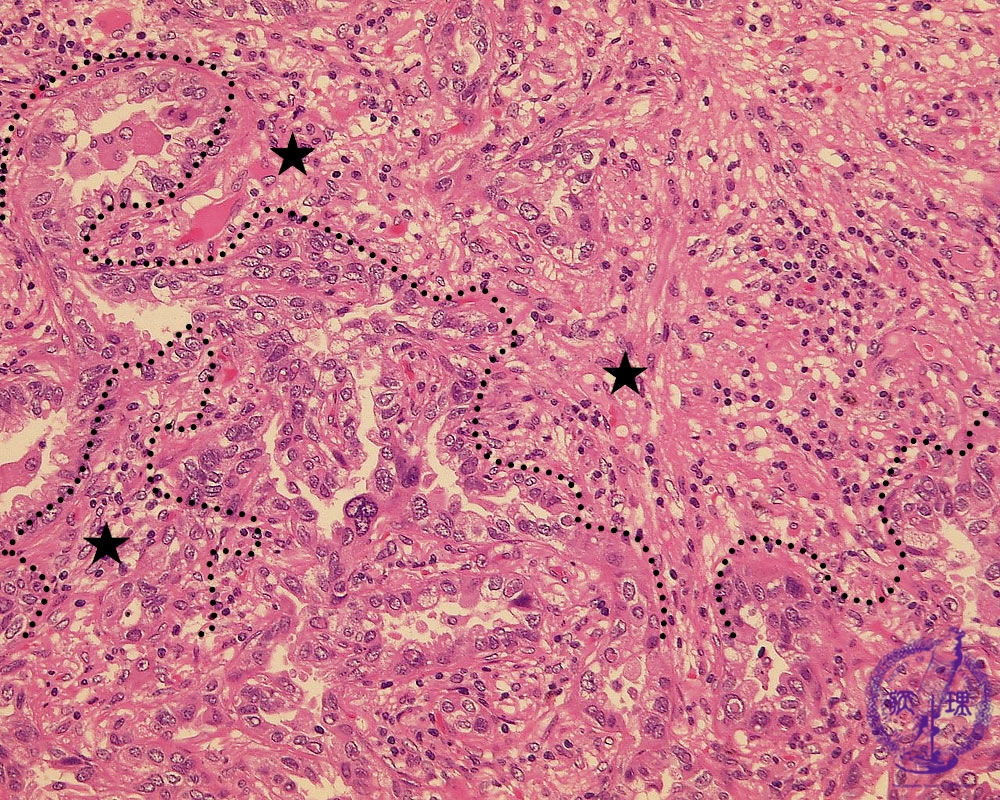

非小細胞肺癌(腺癌)ミクロ像(HE強拡大)

ミクロ像(HE強拡大):腫瘍中心部、浸潤癌の部分では腫瘍細胞は不規則な腺腔を形成しながら浸潤性に増殖している。複雑に入り組んだ間質(星印)にはリンパ球を中心とした炎症細胞の浸潤が見られる。